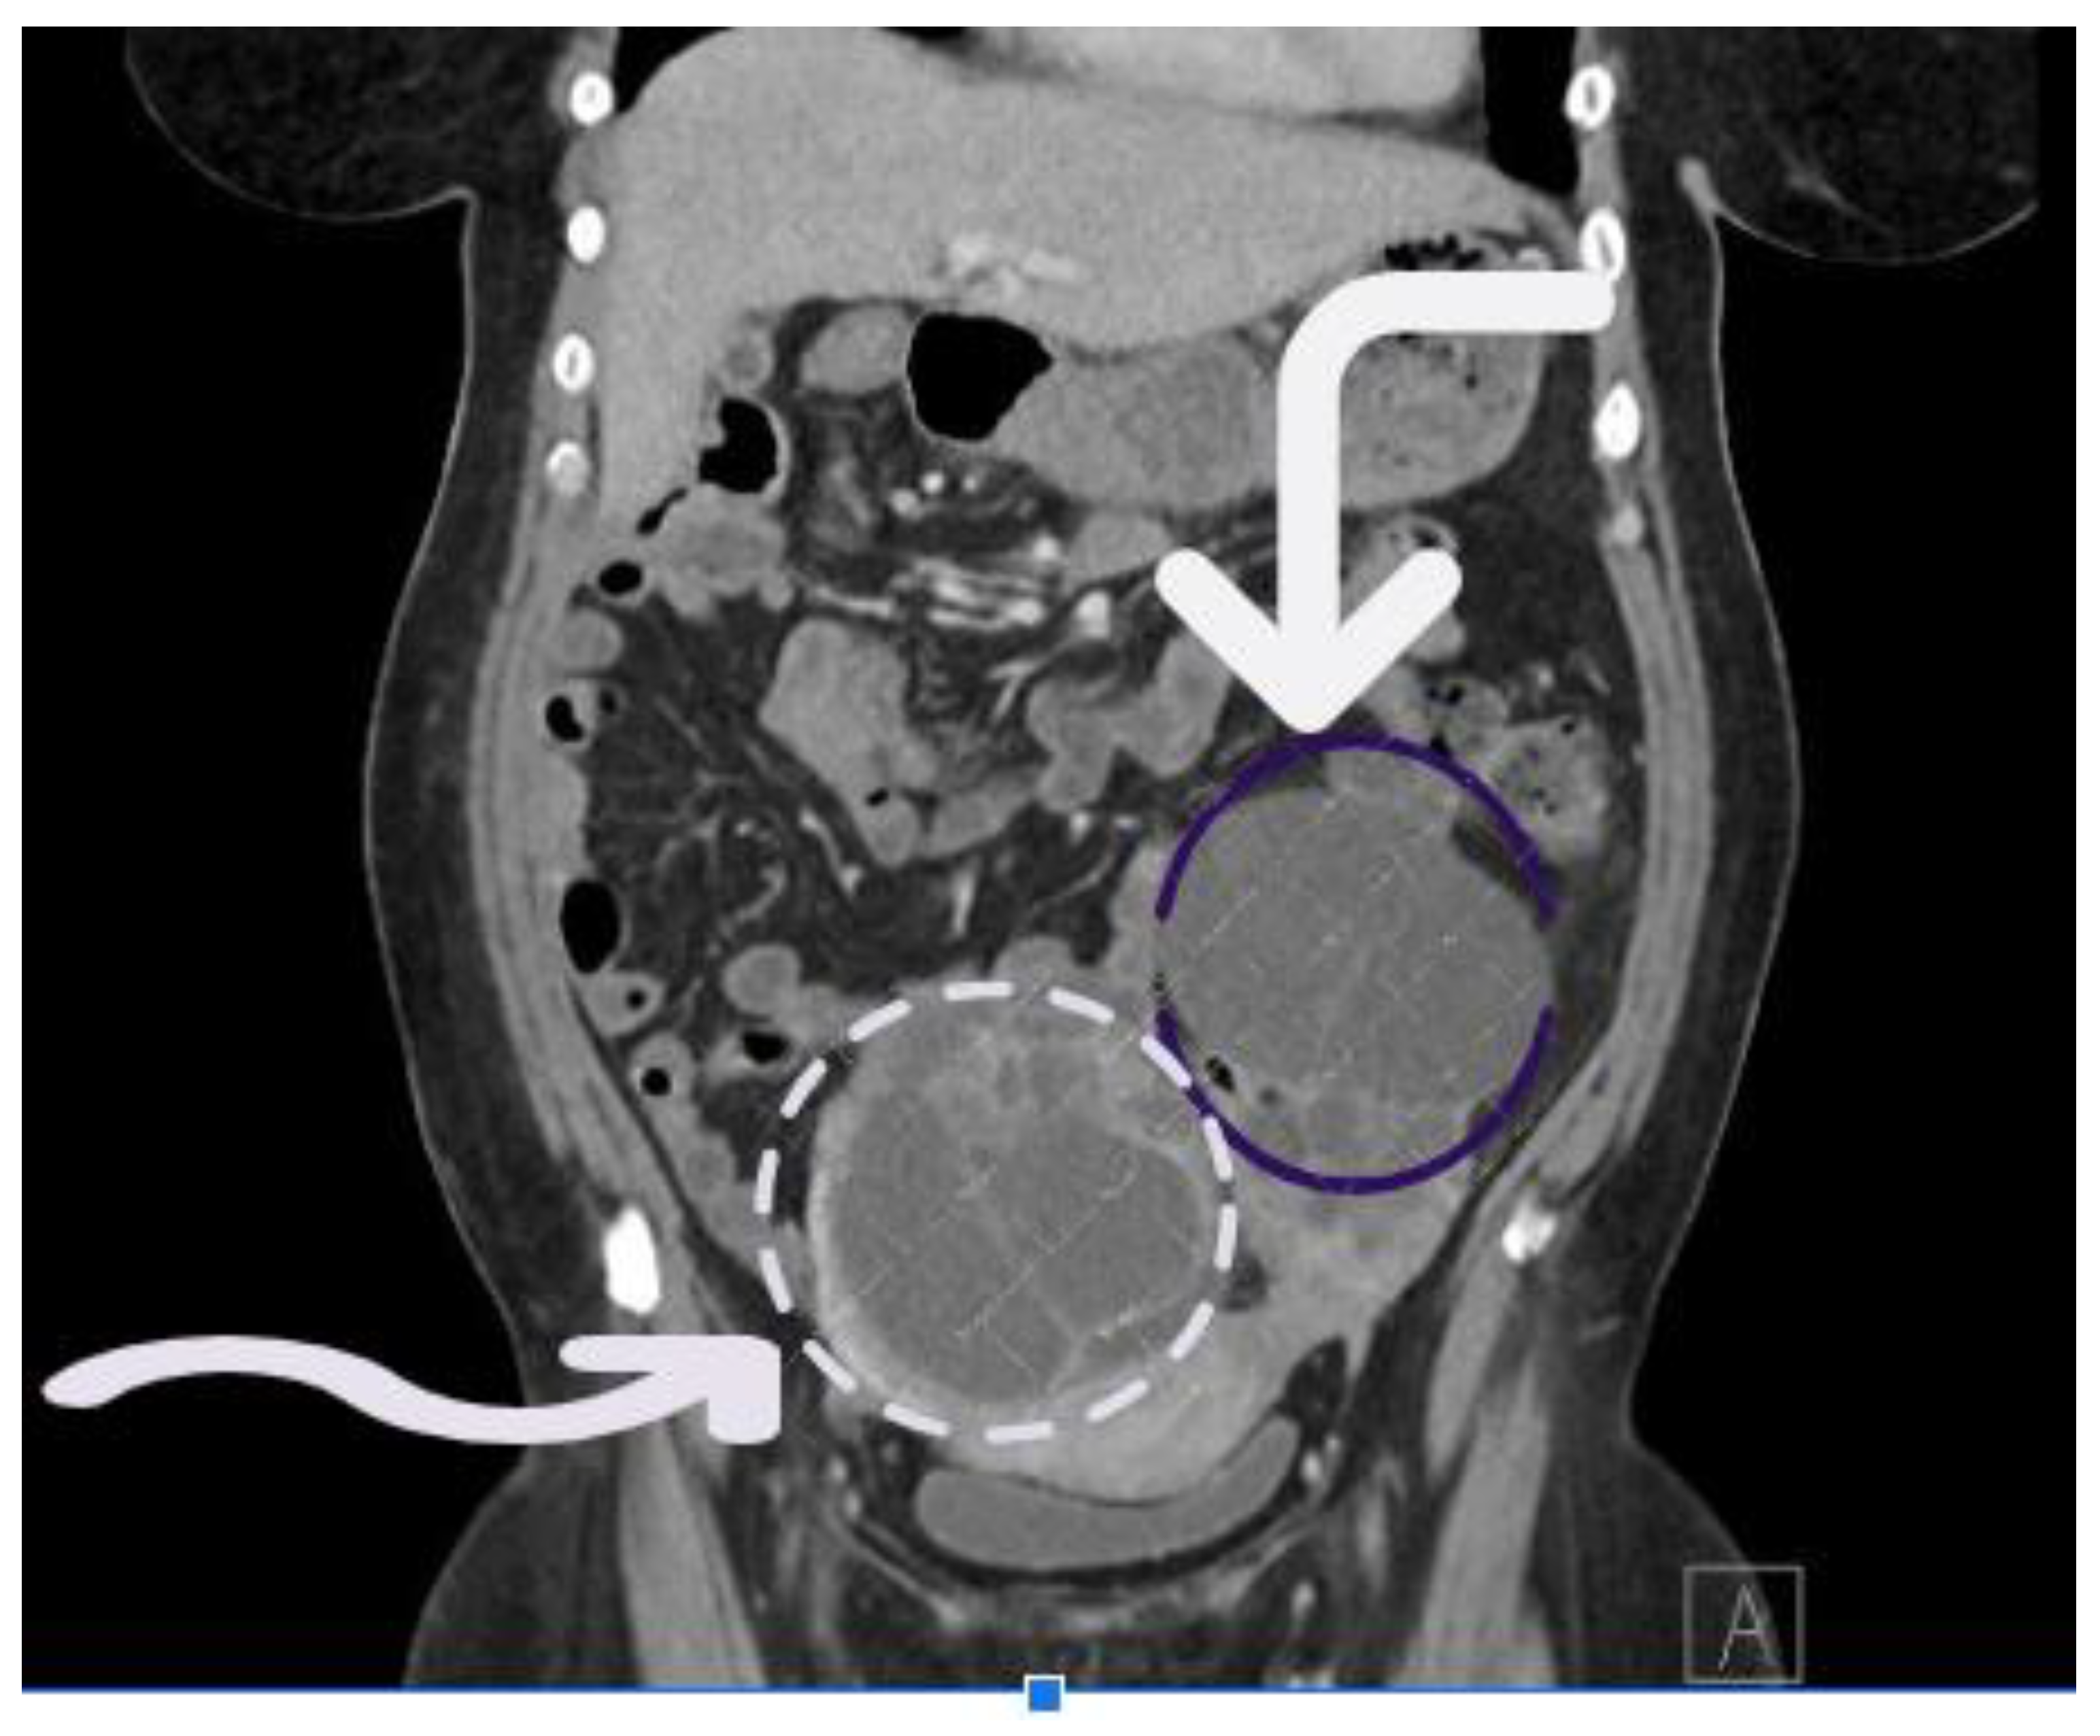

Case Presentation: